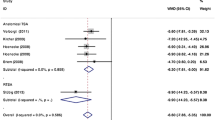

Version error

Mean version error was 5.7 ± 4.7° (aTSA = 5.8 ± 4.4°, rTSA = 5.7 ± 4.8°). Mean version error did not differ based on Favard classification [12] overall (P = 0.297; E0 = 6.0 ± 4.9°, E1 = 6.2 ± 5.0°, E2 = 4.6 ± 3.7°, E3 = 4.6 ± 3.7°, E4 = 4.5 ± 4.9°) nor when stratified by aTSA versus rTSA. No differences in version error were found when grouped (Fig. 3A; P = 0.574). Glenoids without wear had greater version error compared to superiorly-worn glenoids (6.0 ± 4.9 vs. 4.6 ± 3.7, P = 0.041).

Inclination error

Mean inclination error was 7.1 ± 5.6 (aTSA = 4.8 ± 4.8°, rTSA = 8.1 ± 5.7°). Mean inclination error did not differ based on Favard classification [12] overall (P = 0.764; E0 = 7.2 ± 5.6°, E1 = 6.6 ± 5.7°, E2 = 7.4 ± 5.6°, E3 = 8.2 ± 5.7°, E4 = 6.0 ± 5.7°) nor when stratified by aTSA versus rTSA. No differences in inclination error were found when grouped (Fig. 3B; P = 0.833). There was no difference in inclination error between glenoids without wear and glenoids with superior wear (7.2 ± 5.6 vs. 7.8 ± 5.6, P = 0.527) (Figs. 2 and 3).